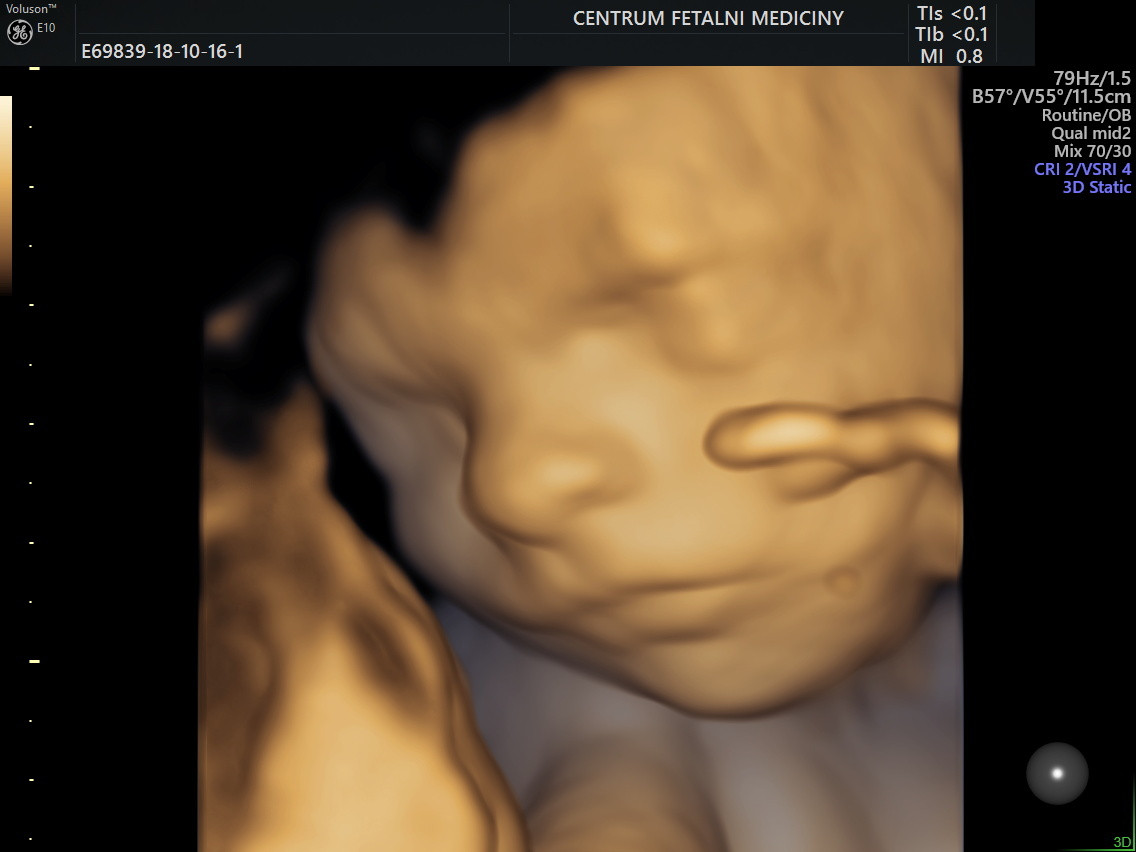

Užitečné pro lékaře a příjemné pro rodiče. Tak lze shrnout zásadní benefity ultrazvukového vyšetření miminka v matčině děloze. Odborníci se díky ultrazvuku dozvědí vše potřebné o vývoji a zdraví dítěte, rodiče se pak mohou na svého potomka podívat, a to nejen při samotném vyšetření. Z Fakultní nemocnice Olomouc si tak mohou odnést klasickou 2D černobílou fotografii, 3D snímek i 4D záznam, tedy rozpohybované 3D snímky ukazující reálný pohyb miminka. Největší zdravotnické zařízení na střední Moravě ale pružně reaguje na technologické novinky a jako jedno z mála pracovišť v České republice nyní nabízí rodičům také 3D model dosud nenarozeného miminka.

„Pokud mají maminky o 3D model zájem, procedura s ultrazvukovým zobrazením trvá zhruba půl až tři čtvrtě hodiny. Využívá se břišní ultrazvuková sonda, maminka ani miminko při tom nejsou zatíženi žádným druhem záření. Model vzniká z upravené 3D fotografie. Samotný tisk pak může trvat až dvanáct hodin,“ sdělil přednosta Porodnicko-gynekologické kliniky FN Olomouc Radovan Pilka, s tím, že na realizaci této žádané novinky mají zásluhu odborníci z Oddělení biomedicínského inženýrství.

Nejlepší doba pro pořízení 3D modelu miminka je 20. – 31. týden těhotenství. Vše se dá zvládnout i během standardní kontroly v rámci centra porodní asistence. „Pro vytvoření modelu se využívá fotografie obličeje miminka,“ dodává profesor Pilka. Porodnicko-gynekologická klinika ale samozřejmě nabízí i tradiční formáty záznamu podoby dítěte: v případě fotografie vytištěný exemplář nebo uložený na flashdisk, u videa pak zapsaný na DVD nebo na flashdisk.